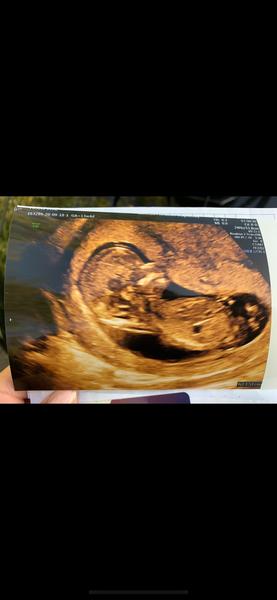

Holky a poznáte něco z mé fotky? Doktorka mi neřekla nic 😃 @danzan taky bych tipovala u tebe holčičku 😊

@levandulka_fialova děkuji, mě přišel hrbolek na jednom obrazku vodorovně...ale doktorka aniž by se podívala řekla nevím asi kluk, je to malý tak já nevím a řekla to tak, že to asi ani nebrat vážně 😀😂

@danzan jestli je to fakt hrbolek, tak tipuju... holku😁